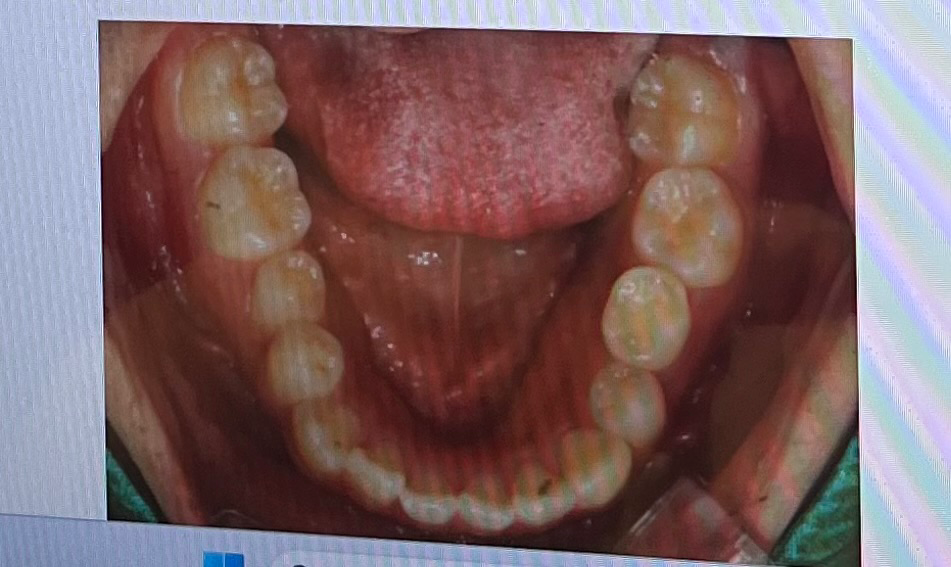

덧니가 심해서 교정 알아보고 있는 중인데요 두 군데 상담 다녀왔는데 한 곳에서는 상악악궁확장을 해야 한다고 하시고 한 곳에서는 굳이 악궁확장 안해도 충분히 할 수 있다고 하시는데 아무리 정보를 찾아봐도 잘 모르겠어서 질문드려요ㅠㅠ

두 곳 다 윗니 두 개 발치 해야 한다고 했고 그 외 상담 내용들도 똑같아서 악궁확장을 진짜 해야 하는건지 안해도 되는건지만 알면 병원 결정하기 쉬울 거 같아요 도와주세욥!!

상악 하악

• 1번 째 사진

• 2번 째 사진

저 사진만으론 판단이 어렵고 교합이 어떤지도 봐야 판단이 됩니다 또한 교정치과의사마다 진단이 다르고 치료계획을 다르게 세울 수 있습니다